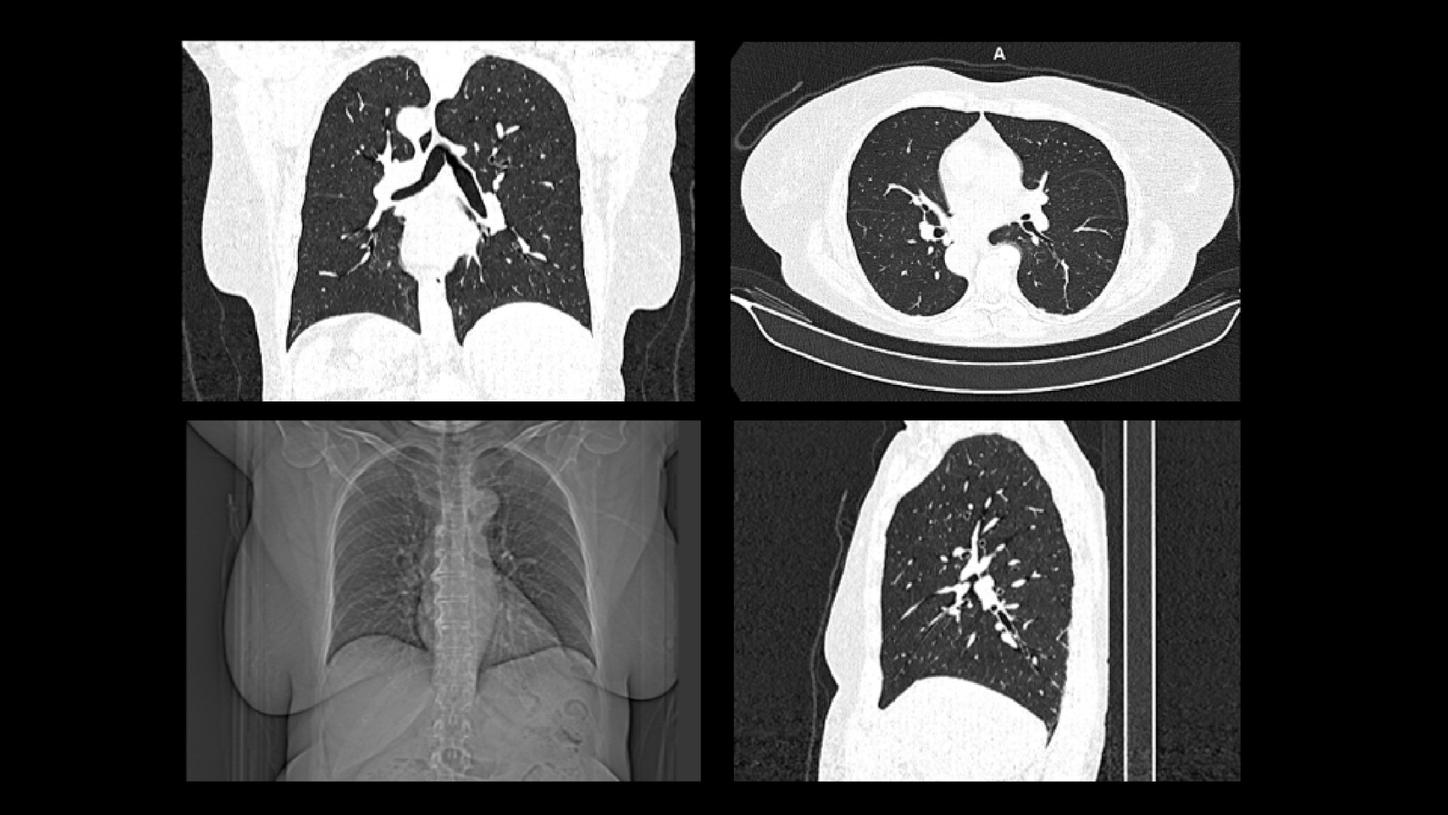

Explore our portfolio of ultra-low-dose CT scanners and AI tools that support you in your diagnostic assessments of lung cancer nodules during screening.